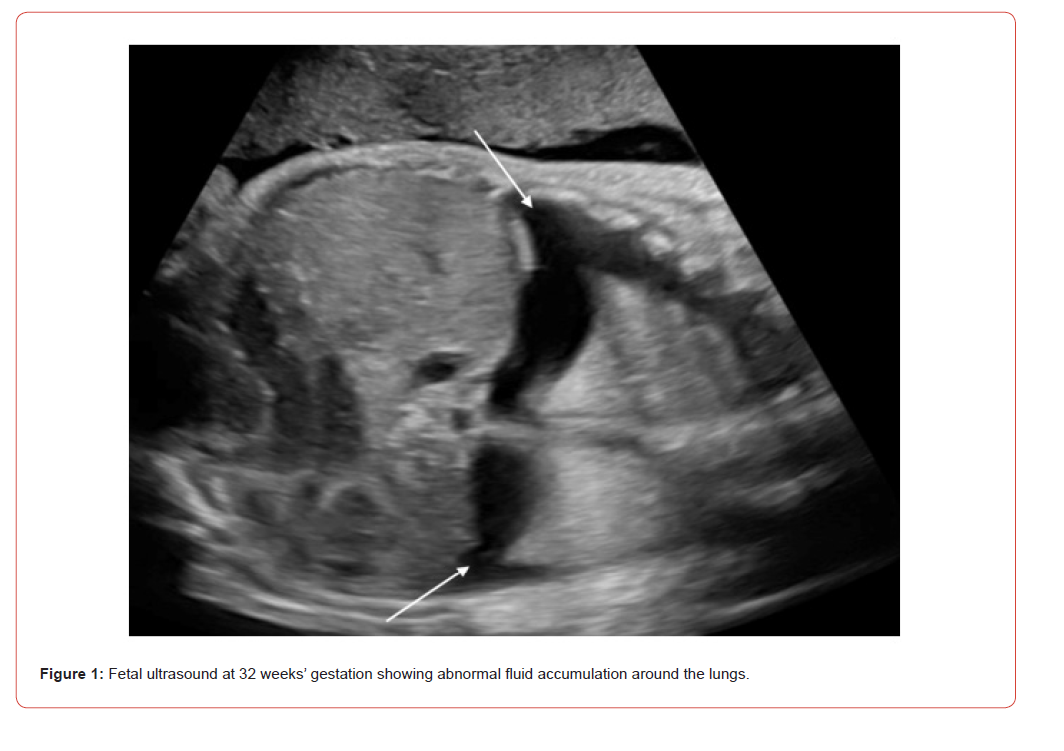

A 3.66 kg female infant born at 35 weeks via cesarean section due to preterm labor was referred to a fetal care center at 32 weeks for evolving hydrops. Ultrasonography showed polyhydramnios and bilateral pleural effusions (Figure 1). Follow-up ultrasound at 33 weeks revealed bilateral pleural effusions, ascites, and scalp edema. Amniotic fluid tests for cytomegalovirus DNA, Toxoplasmosis gondii PCR, and Parvovirus B19 PCR were negative, as was a nonimmune hydrops panel. A chromosomal microarray analysis confirmed a normal female karyotype. Maternal tests were negative for HIV, rapid plasma regain (RPR), and Group B Streptococcus. The maternal blood type was positive and indirect Coombs negative. The patient was diagnosed with Nonimmune hydrops (NIHF).